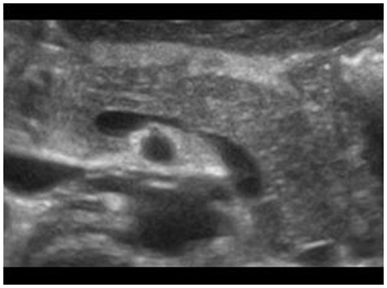

1. Direct Signs (Figure 2)

1. Focal growth

2. Irregularities of the shape

3. Focal hypoechoic parenchyma

Figure 2 Solitary tumor lesion in the body of the pancreas.